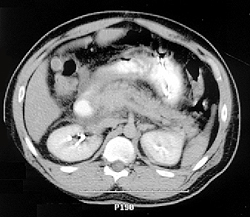

Острый панкреатит (лат. pancreatitis, от -греч. πάγκρεας - поджелудочная железа + -itis - воспаление) - остро протекающее асептическое воспаление поджелудочной железы демаркационного типа, в основе которого лежат некробиоз панкреатоцитов и ферментная аутоагрессия с последующим некрозом и дистрофией железы и присоединением вторичной гнойной инфекции.